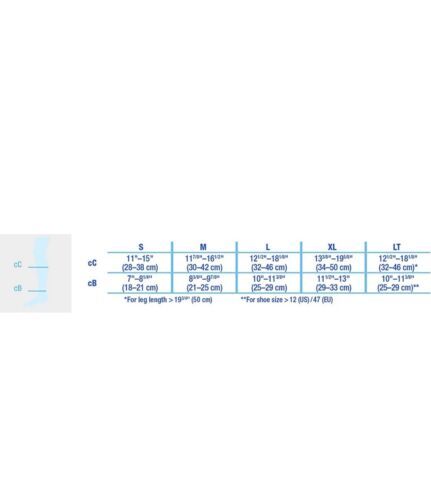

Jobst Mens L Black Set of 2 (1 pair) Medical Legwear Compression Socks Firm 20-30MMHG Open Toe Knee High Ribbed Dress Sock Style. Measures 16" Tall. Excellent Condition, no pulls, rips or stretching. Same or next day USPS Shipping.

Brand: JOBSTSeries: for Men Compression: 20-30 mmHg Style: Knee HighFabric:71% Nylon, 29% Spandex